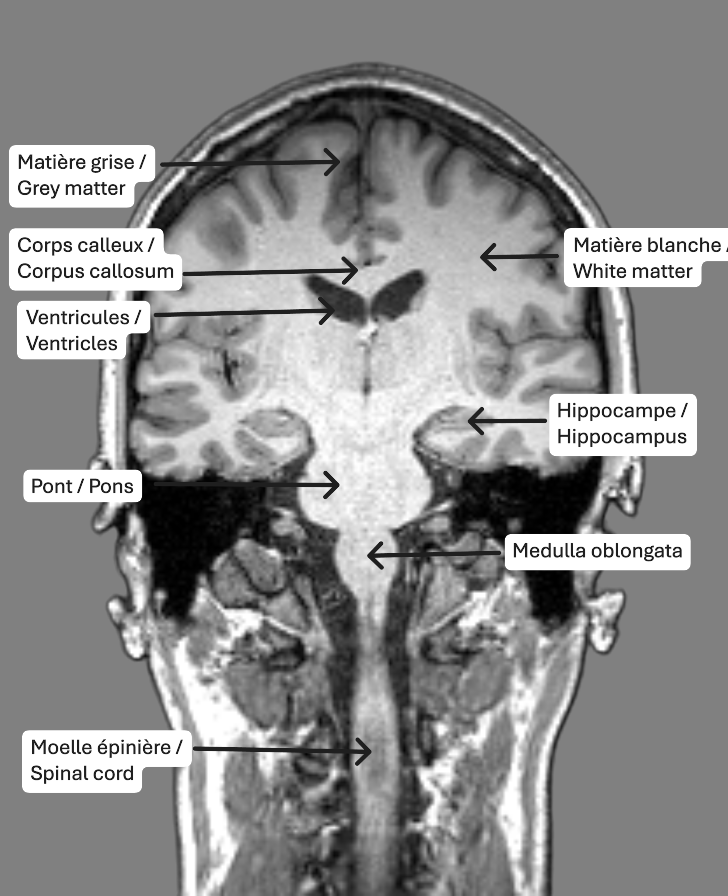

On retrouve trois plans de coupe utilisés dans les images en IRM structurelle, soit les plans axial (transversal) coronal et sagittal. Ce sont différentes façons de sectionner le cerveau qui nous permettent d’observer des structures spécifiques. Le plan axial correspond à un découpage du cerveau du bas vers le haut. Le plan coronal fait référence à des coupes de l’arrière vers l’avant du cerveau. Finalement, le plan sagittal est une façon de diviser le cerveau de la gauche vers la droite.

Identification des structures

Les tissus les plus facilement identifiables sur les images IRM pondérées en T1 sont les ventricules, la matière blanche et la matière grise. Les ventricules, en noir, sont des cavités contenant le liquide cérébrospinal, qui circule également dans les méninges. La matière blanche est constituée des axones des neurones et des connexions entre ceux-ci, et est représentée en gris pâle. En gris foncé, on retrouve la matière grise, qui comprend les corps cellulaires des neurones.

Pilot MRI Data from the Douglas Research Centre